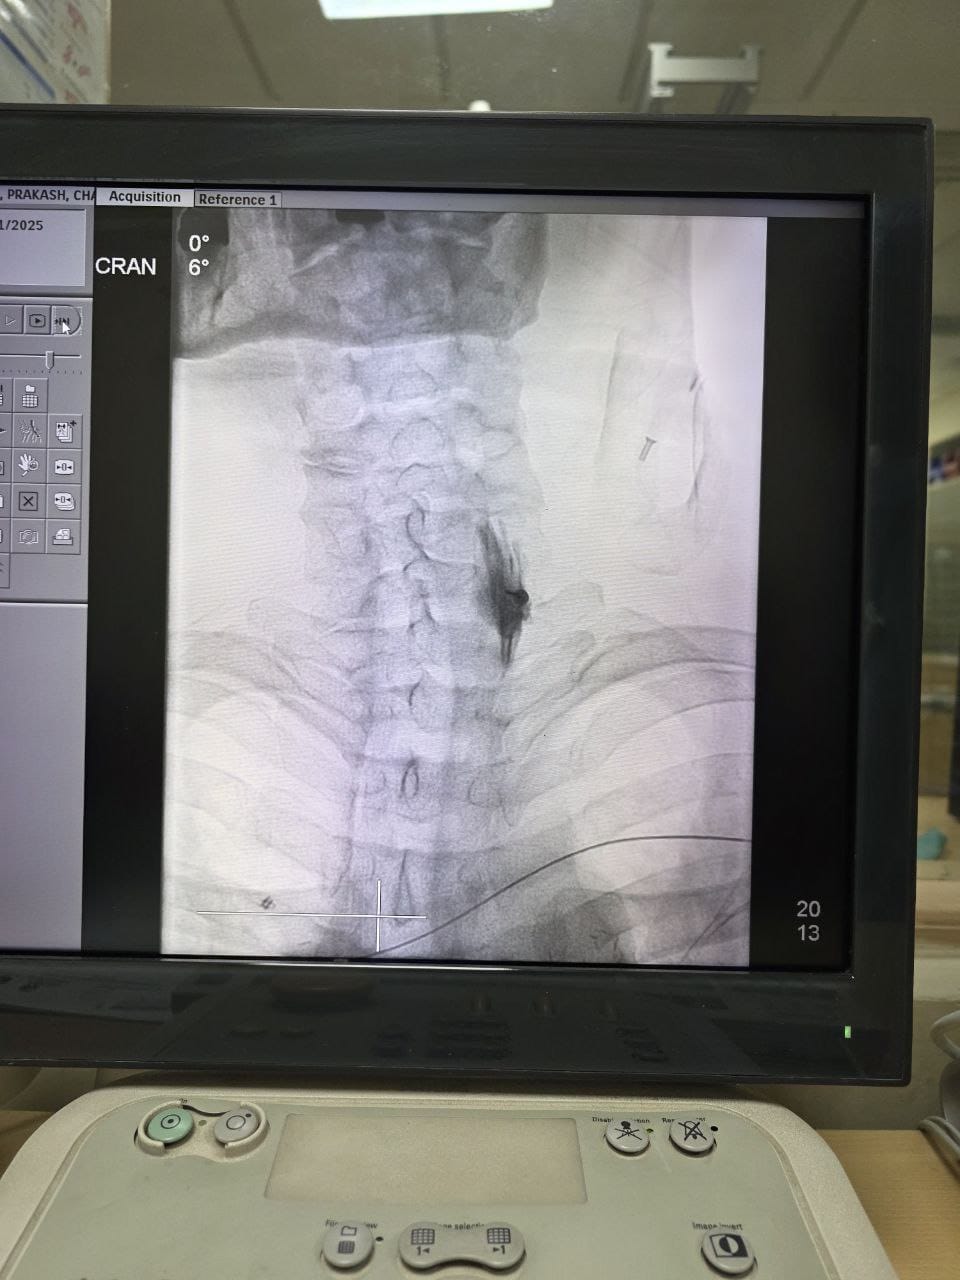

Procedures